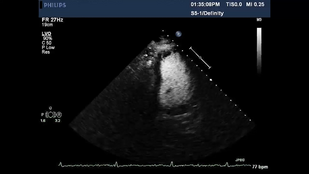

• Обложка: Рис. 2.14 Усиление Видео А Аортальный клапан, коэффициент усиления снижен

• Обложка: Рис. 2.14 Усиление. Видео В Коэффициент усиление повышен